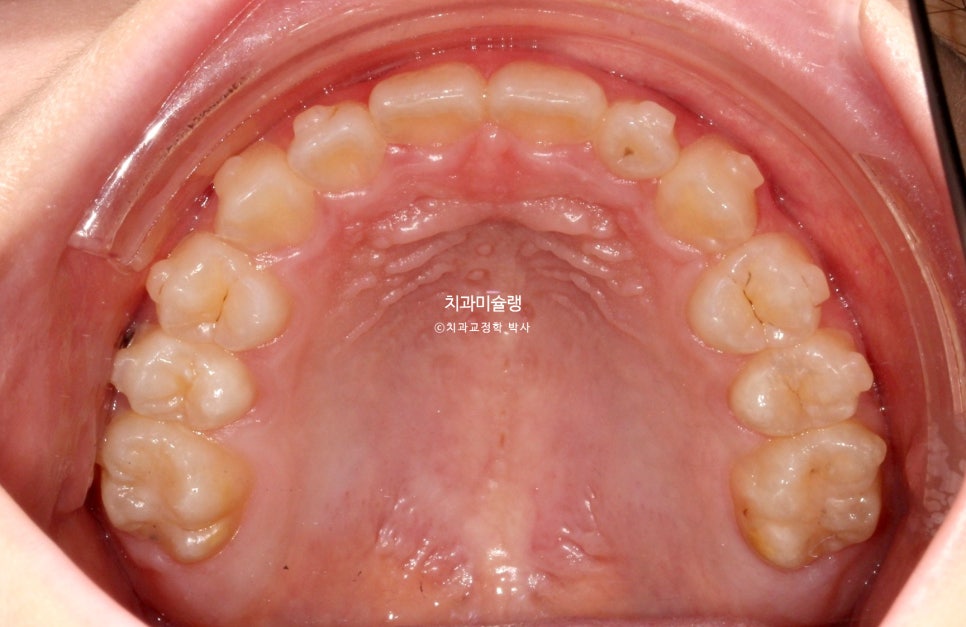

2024년 6월 초진 상태

24년 6월, 교정치료를 위해 내원한 만 10세 어린이 입니다.

송곳니 덧니와 개방교합이 보입니다.

고치고 싶은것은 ‘덧니’ 입니다.

위 앞니가 아래 앞니를 덮지 못하고 아래 앞니가 더 앞으로 나가있는 반대교합 입니다.

안모에서는 아래턱이 발달한 주걱턱 양상이 보입니다.